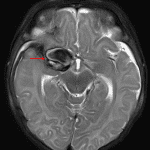

Age: 2 months

Sex: Female

Indication: Fussiness, bulging anterior fontanelle

MRI

Giant cerebral aneurysm